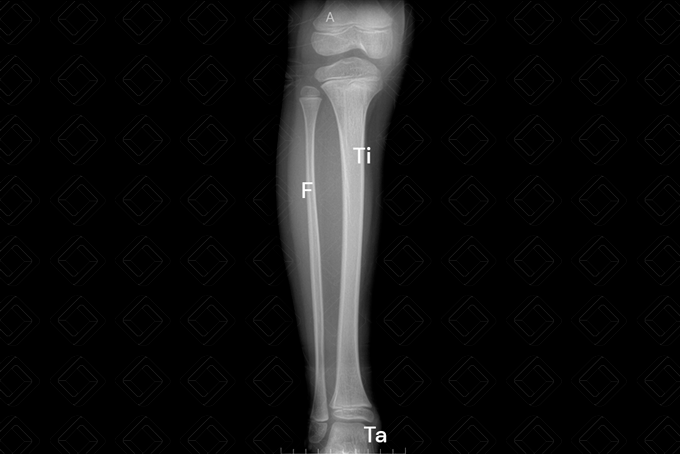

Radiografia da perna direita/esquerda AP e perfil.

Texto alternativo para a imagem Radiografia da perna direita AP. Créditos: Athena Hub/Medical Harbour

Legenda: F = fíbula; P = patela; Ta = tálus; Ti = tíbia.